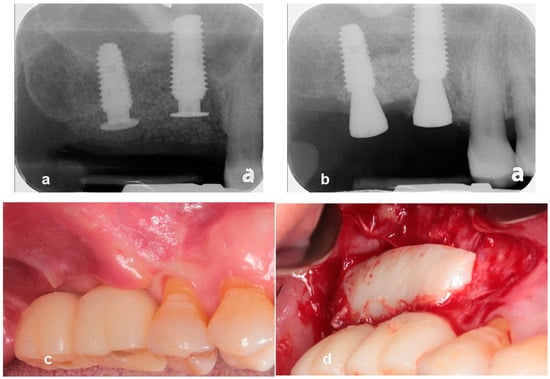

- Woo, R.H.; Kim, H.G.; Kim, G.; Park, W.E.; Sohn, D.S. Simplified 3-dimensional ridge augmentation using a tenting abutment. Adv. Dent. Oral. Health 2020, 12, 185–205. [Google Scholar]

- Sohn, D.S. Reconstruction of three-dimensional alveolar ridge defects utilizing screws and implant abutments for the tent-pole grafting’ techniques. In Essential Techniques of Alveolar Bone Augmentation in Implant Dentistry, 2nd ed.; Tolstunov, L., Ed.; Wiley Blackwell: Hoboken, NJ, USA, 2023; pp. 404–418. [Google Scholar]